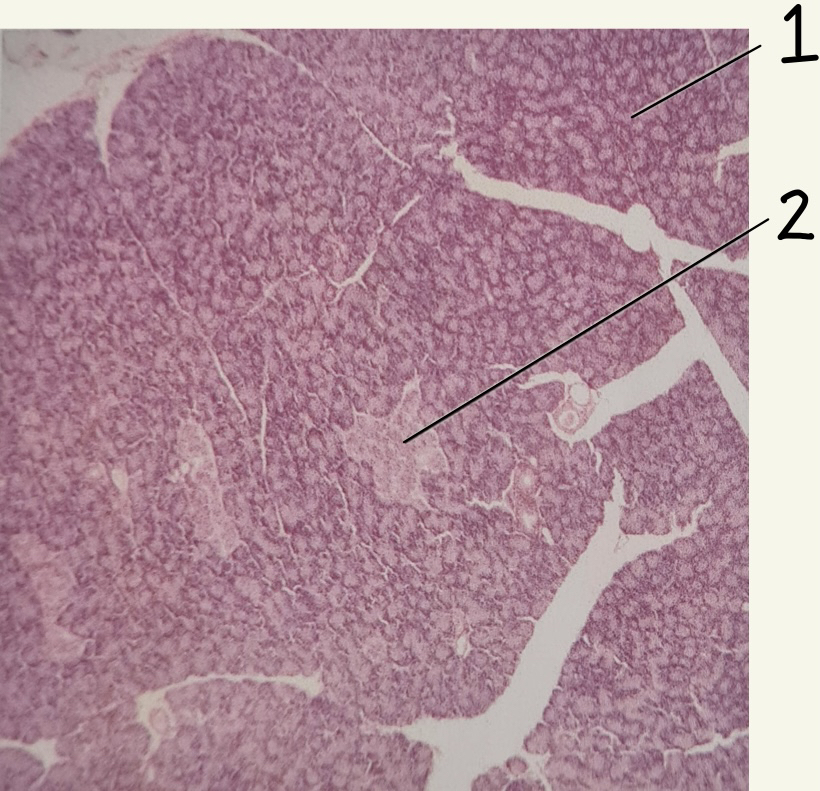

Pancreas slide

1. Acinar cells

2. Pancreatic islet